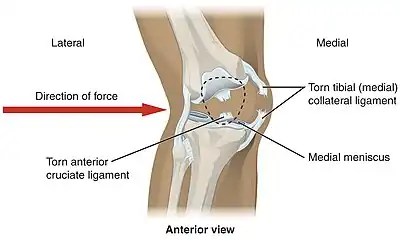

Lateral trauma to the knee can tear the medial collateral ligament, anterior cruciate ligament, and medial meniscus

Knee pain is caused by trauma, misalignment, degeneration, and conditions producing arthritis.[29] The most common knee disorder is generally known as patellofemoral syndrome.[29] The majority of minor cases of knee pain can be treated at home with rest and ice, but more serious injuries do require surgical care.[29]

In sports that place great pressure on the knees, especially with twisting forces, it is common to tear one or more ligaments or cartilages. Some of the most common knee injuries are those to the medial side: medial knee injuries.[32]